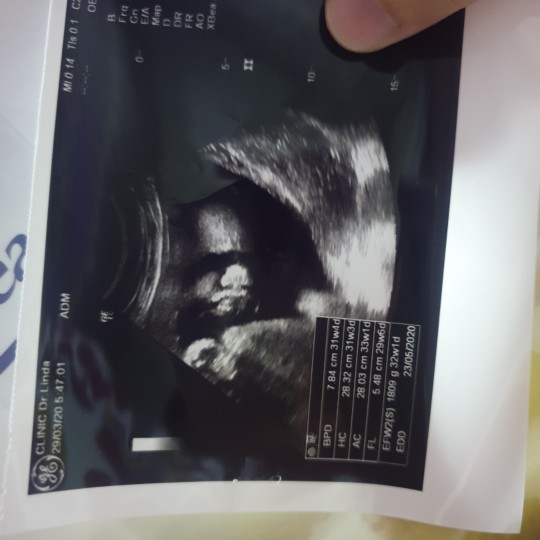

มีคนมาว่าแม่นับวันผิดบ้างหละ คลอดก่อนกำหนดบ้างหละ คือรูปนี้นานแล้ว ตอน16wแล้ว แม่ลงนานแล้วนะค้ะ ตอนนี้ก็ 28wละจ้าา บ้านนี้กำหนดคลอด28มิ.ย.63 เพศชายจ้า?